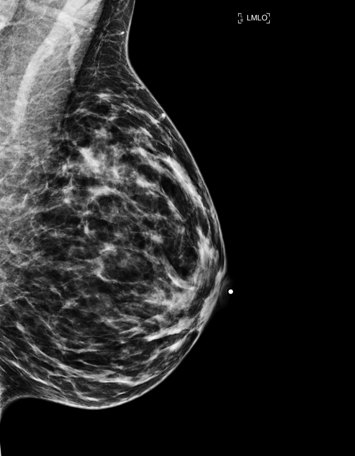

- Imagerie du sein / Mammographie

La mammographie de dépistage est une radiographie des seins qui permet de détecter une lésion de petite taille qui souvent ne serait pas palpable. Habituellement, deux radiographies sont nécessaires pour chaque sein : une vue de face et une vue oblique.